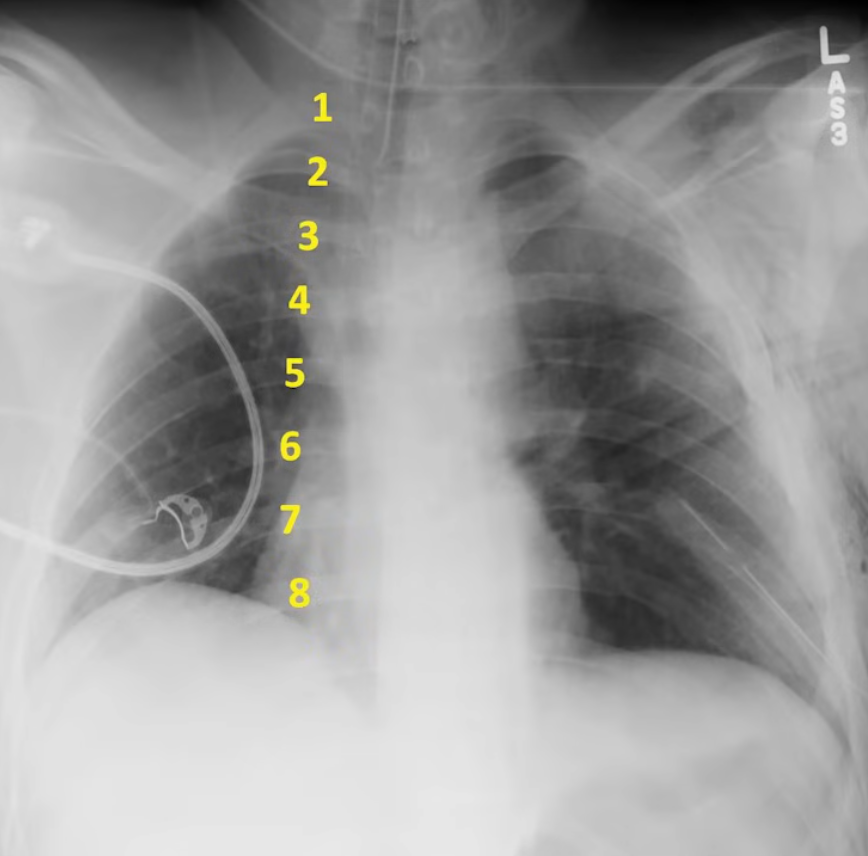

Lines, Tubes, Devices, Surgeries

- Optimal placement of a central line and PICC lines places the tip at he junction of the SVC and right atrium

- PA Catheter (Swan-Ganz catheter). Optimal placement places the tip at the level of the hilum, no more than 3 cm right of midline or 1 cm beyond the cardiac silhouette

- Proper placement of endotracheal tubes results in the tip being ~5cm above the carina

- Nasogastric tube placement is confirmed by:

- Descent through the thorax centrally

- Crossing the diaphragm

- Once below the diaphragm, initially deviates to the left

- Optimally, tip should be >10 cm below the gastroesophageal junction